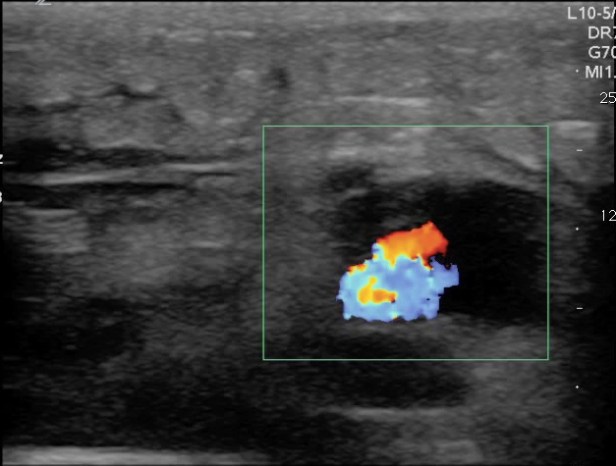

Now that you have identified an abscess the immediate reaction is to stick a knife in it right? Before that however, apply color flow to the abscess. If the abscess is adjacent to a vessel the entire area may appear anechoic and vessels can look like part of the abscess. Using color flow will identify the blood vessel and avoid iatrogenic injury.

FIGURE 8. ABSCESS WITHOUT COLOR FLOW INTERROGATION.

FIGURE 9. THE SAME ABSCESS WITH COLOR FLOW INTERROGAITON DEMONSTRATING AN ADJACENT BLOOD VESSEL.